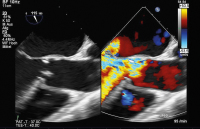

Aortenklappeninsuffizienz: Was gibt es Neues? // Aortic valve regurgitation – What do the 2021 guidelines say? What has changed from 2017?

Journal für Kardiologie - Austrian Journal of Cardiology 2024; 31 (5-6): 120-128 Volltext (PDF) Summary Abbildungen